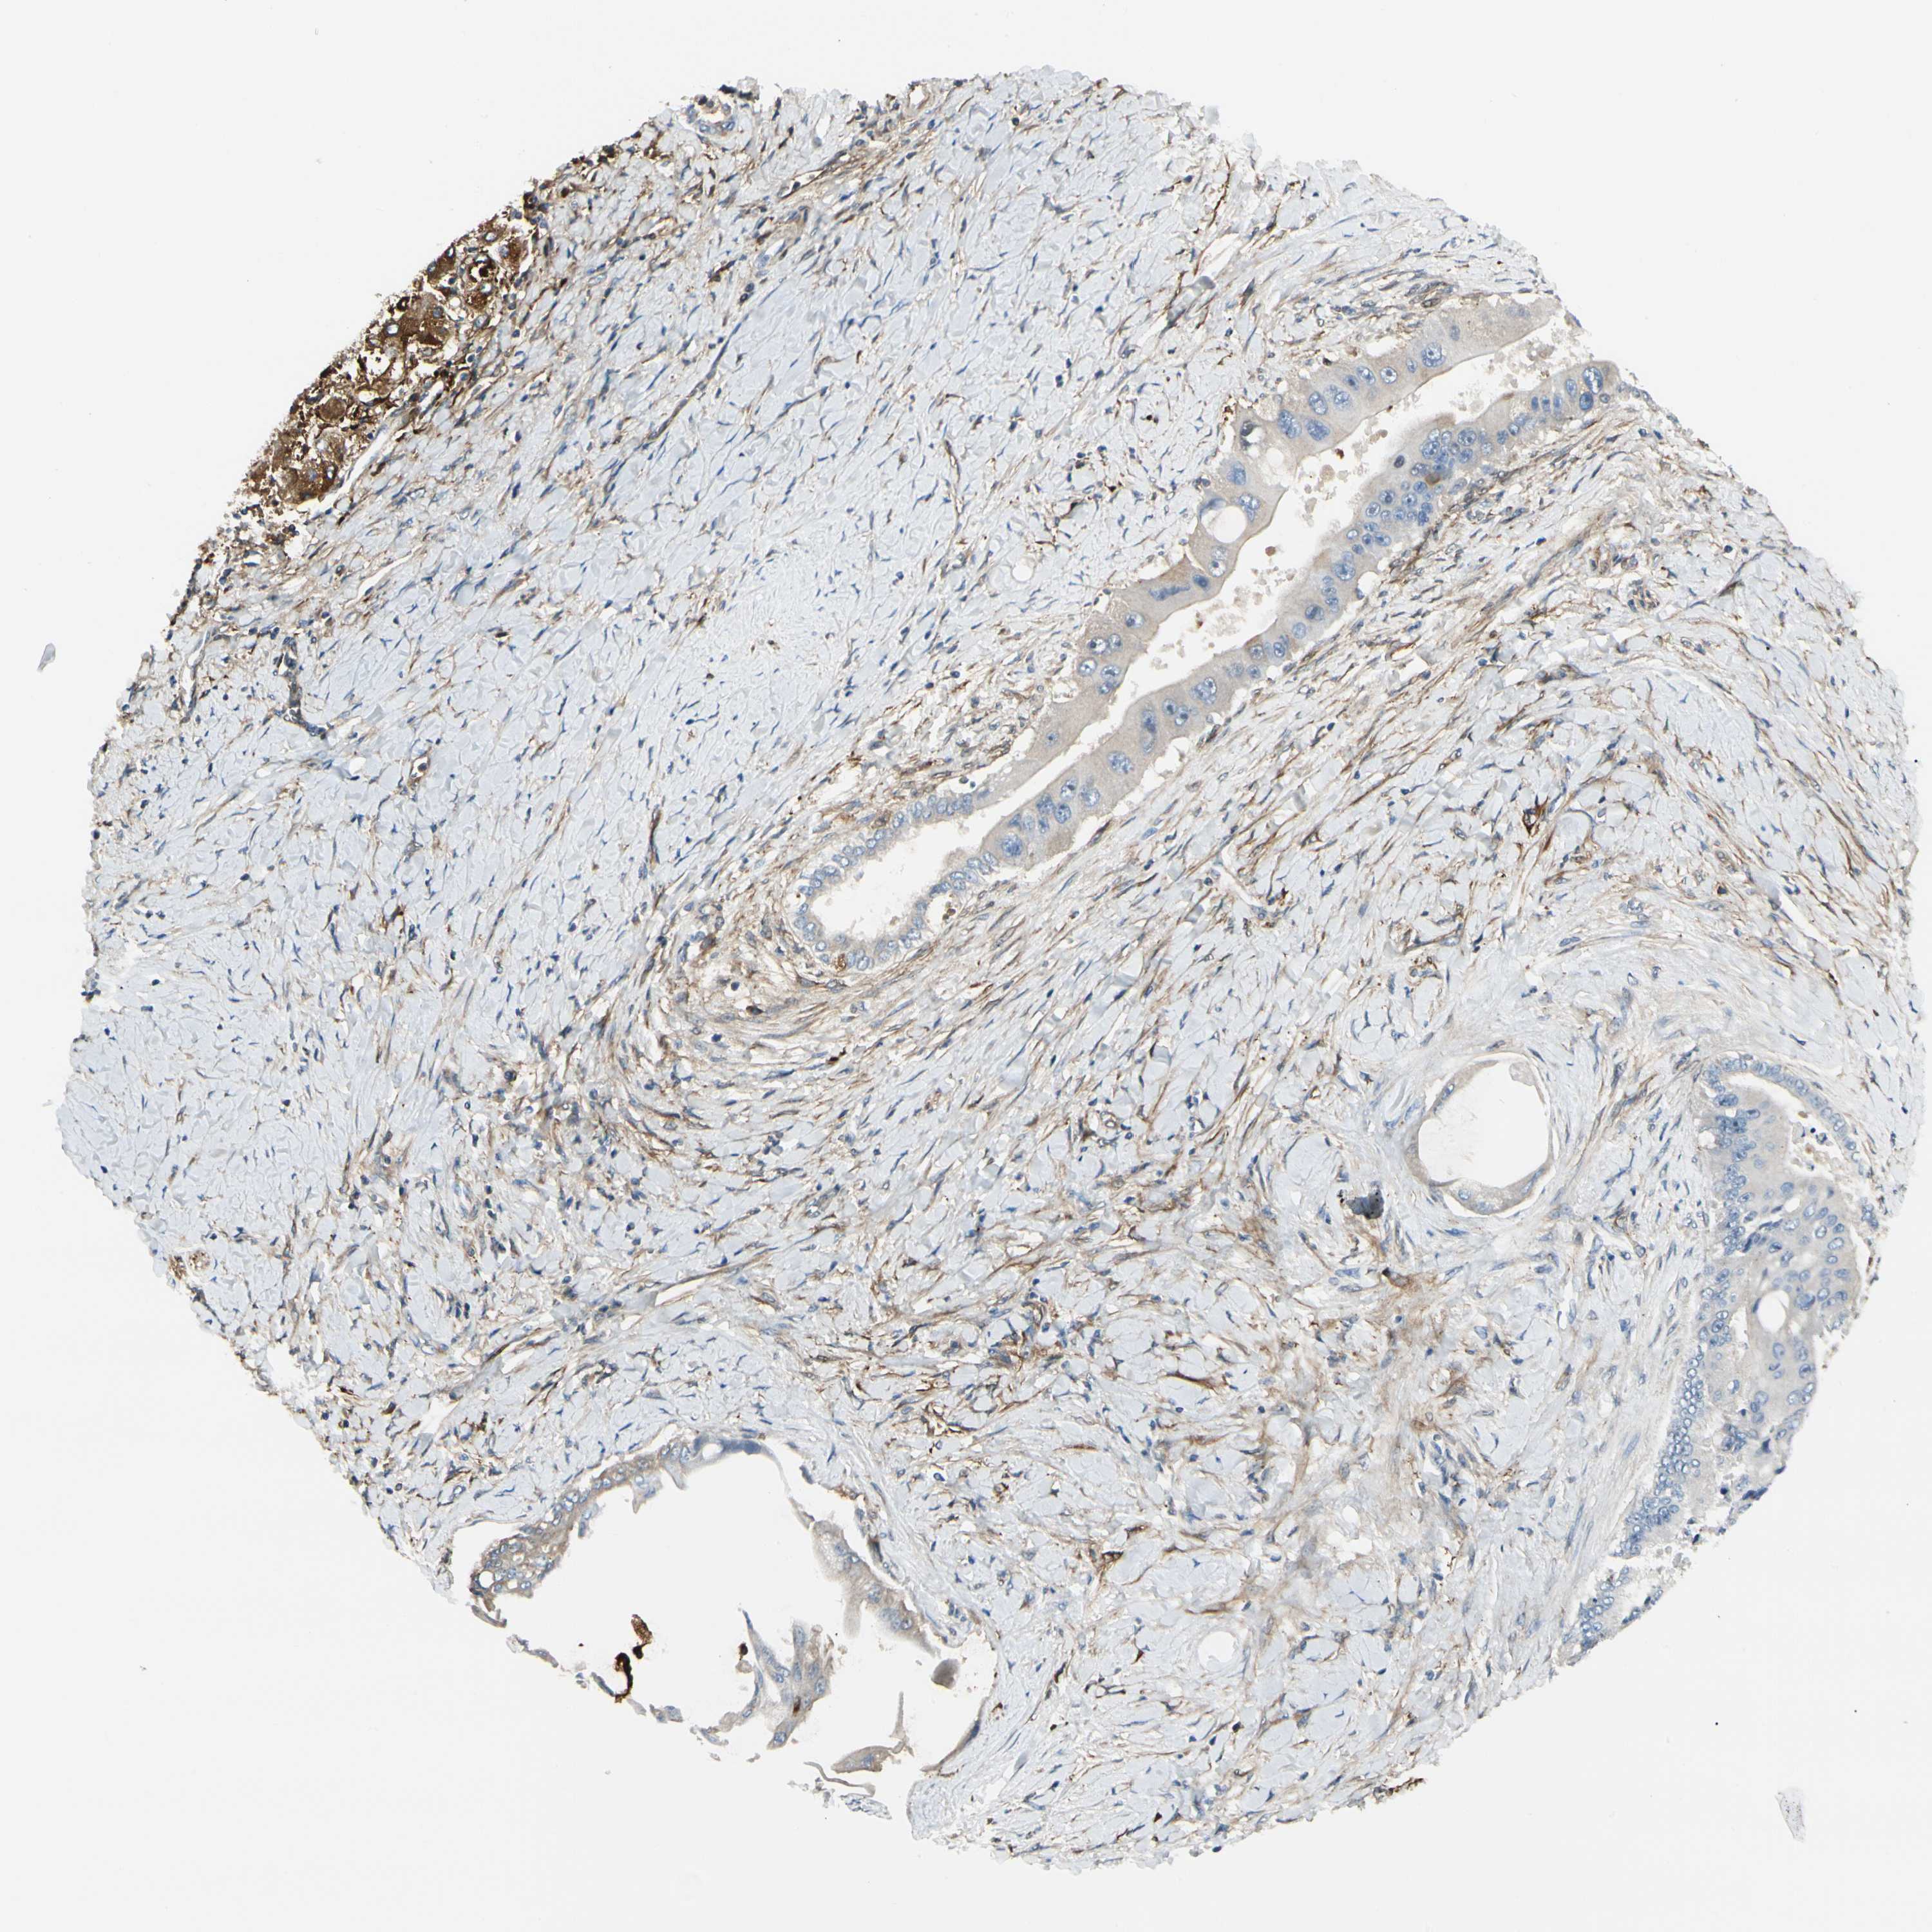

LIVER CANCER - Protein expressioni

A mouse-over function shows sample information and annotation data. Click on an image to view it in a full screen mode. Samples can be filtered based on level of antibody staining by selecting one or several of the following categories: high, medium, low and not detected. The assay and annotation is described here.

Note that samples used for immunohistochemistry by the Human Protein Atlas do not correspond to samples in the TCGA dataset.

Antibody stainingi

Antibody staining in the annotated cell types in the current human tissue is reported as not detected, low, medium, or high, based on conventional immunohistochemistry profiling in selected tissues. This score is based on the combination of the staining intensity and fraction of stained cells.

Each image is clickable and will lead to virtual microscopy that enables deeper exploration of all samples and also displays staining intensity scores, fraction scores and subcellular localization as well as patient and tissue information for each sample.

Antibody CAB008623

Staining

High

Medium

Low

Not detected

Intensity

Strong

Moderate

Weak

Negative

Quantity

>75%

75%-25%

<25%

None

Location

Nuclear

Cytoplasmic/membranous

Cytoplasmic/membranous,nuclear

Cholangiocarcinoma

Carcinoma, Hepatocellular, NOS